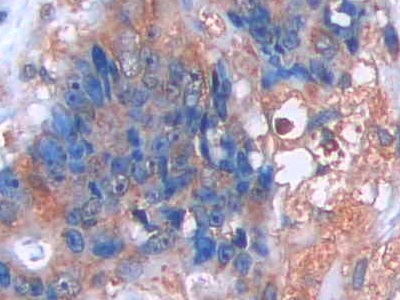

IHC (Immunohistochemistry)

(DAB staining on IHCP; Sample: Human Colorectal cancer Tissue; Primary Ab: 40ug/ml Mouse AntiHuman CCK8 Antibody Second Ab: 2ug/mL HRPLinked Caprine AntiMouse IgG Polyclonal Antibody (Catalog: SAA544Mu19))